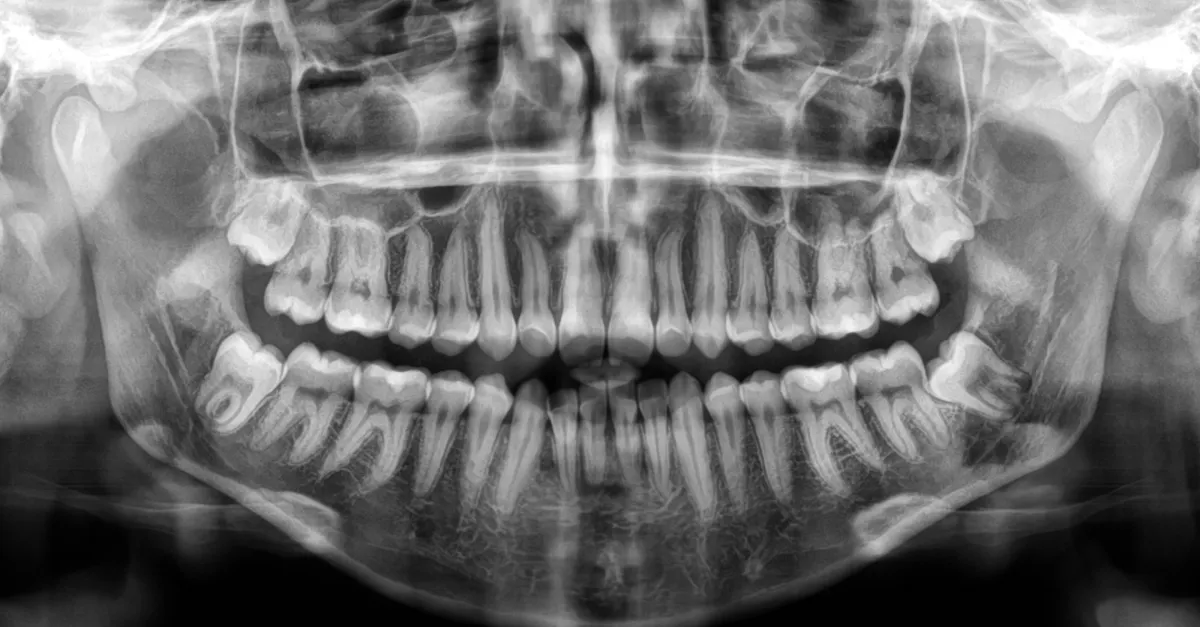

LICÓWKI PORCELANOWE Licówki to cienkie 0,5 mm porcelanowe płatki naklejane na zęby. Jest to świetne rozwiązanie aby uzyskać piękny ,naturalny uśmiech bez konieczności szlifowania zębów i osadzania na nich koron. To mało inwazyjny sposób na osiągnięcie wymarzonego efektu. Licówki pozwalają […]